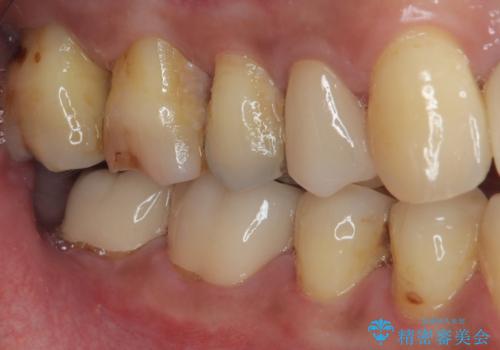

- 銀歯を外して虫歯治療をしたいとのことで来院された患者様です。右下の7番目の歯は銀歯の下に虫歯が広がっており根管治療の可能性もあることを説明したうえで治療を行いました。

左下の5番目の歯はセラミックインレー修復で治療を行うことにしました。

左下の7番目の歯は仮歯に置き換えた後自発痛、咬合痛の所見を認めたので、当院院長である藤巻先生に担当してもらっています。